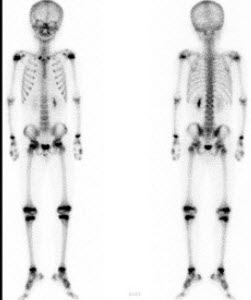

男,8岁,小脑星形胶质细胞瘤术后5个月,未诉不适,行99Tcm-MDP骨显像如图,对此影像描述正确的是()

A.四肢骨浓聚影为骺板

B.肋骨肋软骨关节浓聚是正常的

C.颅缝浓聚提示病理过程的出现

D.四肢长骨显影清晰是不正常的

E.任何骺板形态和放射性的改变都提示病理过程的出现